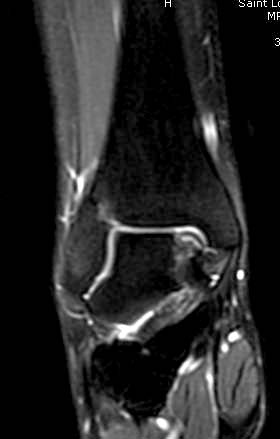

Доброго времени суток, уважаемые коллеги. Прошу помочь определиться с тактикой лечения. Пациентка 40 лет, в течение последних 8-9 мес. беспокоила боль в левом голеностопном суставе после значительной физической нагрузки (по роду деятельности вынуждена проходить в день не менее 15 км). Факт травмы отрицает. Лечилась самостоятельно, мазями и приемом НПВП. В последнее время боль стала возникать после умеренной нагрузки, присоединились отек и хромота. Прием НПВП и ограничение нагрузки до уровня бытовой болевой и отечный синдром купируют. Обратилась к нам, выявлены изменения таранной и пяточной кости, представленные на КТ. Вопрос: единственным ли выходом является артродез или можно обойтись менее радикальным вмешательством? Смущает невыраженная клиника и молодой возраст пациентки... Будем рады любой помощи со стороны уважаемого сообщества. А. Баженов, г. Екатеринбург

Разбираемый случай не имеет ничего общего с классическим Аваскулярным Некрозом Таранной кости. Здесь так назывемый (osteochondral defect) или osteochondritis dissecans (OCD) таранной кости, при котором патология локализуется в медиально-верхнем нагрузочном отделе. В основном OCD

встречается после хронической травмы, но бывают случаи врожденного генеза, которые обнаруживаются при случайных исследованиях.

Симптоматология OCD выражается слабым отеком, а более сильные боли наступают после физической нагрузки. В отличие от АВН тарана, когда боли постоянные, а при OCD боли изчезают после отдыха. В начальных стадиях

на рентгенограммах не всегда заметны склерозные участки, и поэтому в большинстве диагноз устанавливается поздно. Приход КТ и МРТ улучшил диагностику, и в срезах внутри кисты можно увидеть жидкость, но это не означает проявление симптоматологии. Симптомы проявляются с момента образования внутрисуставных краевых фрагментаций!